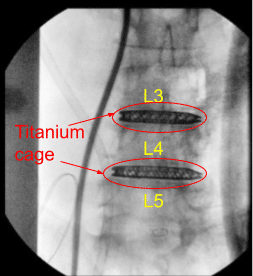

Intraoperative X-ray

AP and lateral radiographs were used to position him in a true lateral and AP position with his spinous processes equidistant from the pedicles and with his residual endplates crisp on lateral fluoroscopy. The left flank position was then carefully scrubbed, prepped and draped after two separate transverse flank incisions were marked out overlying the L3-L4 and L4-L5 disc spaces under fluoroscopy.

Stimulation was carried out and found to have no neural elements whatsoever in proximity through a transversalis dilatation. The MaXcess dilator was docked at the posterior third of L4-L5 disc space under lateral fluoroscopy and affixed in place with a K-wire.

After AP and lateral radiographs confirmed excellent positioning at the posterior third of the L4-L5 vertebral body, the MaXcess retractor was affixed in place with the articulating arm and the interior of the MaXcess retractor was carefully inspected with visual confirmation of no neural elements within the blades.

Once we were certain that the disc space was prepared for arthrodesis, an 8 x 55 x 22 mm lordotic 3D printed titanium cage was selected from the NuVasive tray and impacted into place at the L4-L5 disc space. Excellent indirect decompression and completion of L4 neuroplasty was seen with separation of the L4 and L5 vertebral bodies.

Serial bullet trials were impacted into the L3-L4 disc space to complete an indirect decompression and neuroplasty of the exiting L3 nerve roots. The bony endplates were then aggressively prepared with a ring curette following withdrawal of the bullet paddles. An 8 x 50 x 22 mm lordotic CoRoent titanium cage from the NuVasive tray was then directly impacted into L3-L4 disc space to complete the arthrodesis.

AP and lateral radiographs indicated excellent cage positioning, restoration of lordosis, and indirect decompression throughout. Accordingly, the L3-L4 cage was released from the cage inserter. The area was copiously irrigated with antibiotic impregnated saline and packed with Surgiflo hemostatic matrix product.